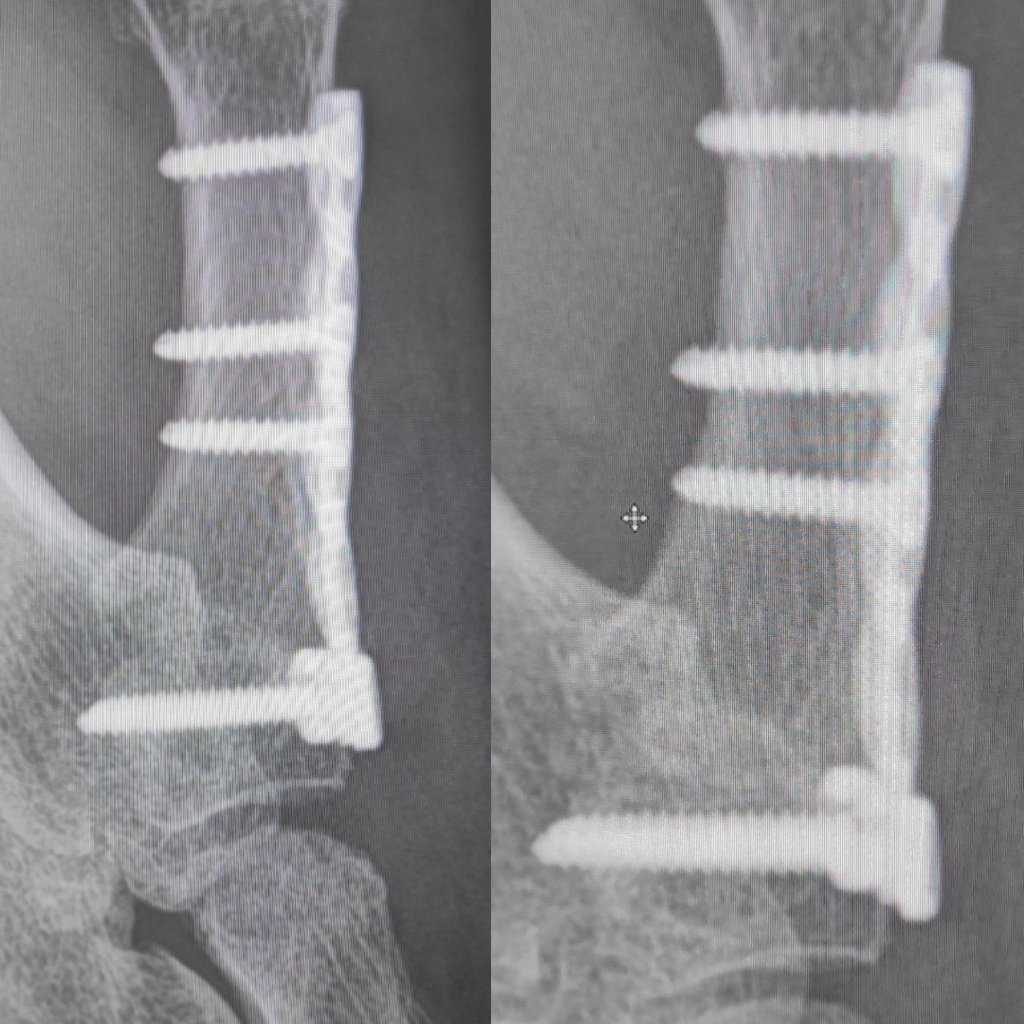

Good news the bone is healing nicely, so the splint is no longer needed. Exercise wise I’m doing all I need to do. We had a discussion over the Right hand though, we had planned the exact same surgery for this side. However the bone stock isn’t there, and it’s far more complex as it involves more joints. They are thinking of a silicon implant and pin. And not do the middle finger at the same time as previously planned, as the thumb is complex enough without adding more.